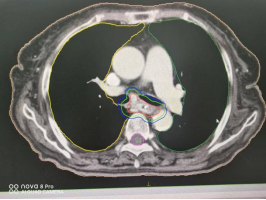

1、肺癌横断面及矢状面肿瘤处治疗剂量显示图

3、计划系统效果图:黄色线内-蓝色线外深颜色区域为高剂量区域,黄色线外及蓝色线内为低剂量区域。即照射剂量区域可按肿瘤治疗的需要进行调节。